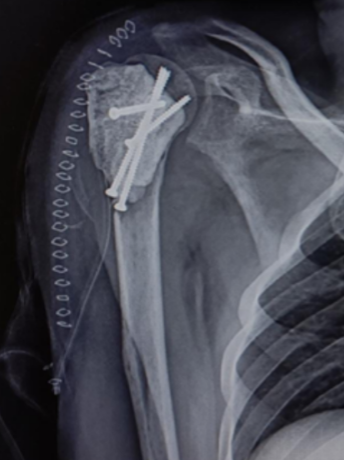

A Novel Approach to Proximal Humerus Giant Cell Tumor: Cement Spacer and Screw Interdigitation for Optimal Stability

Kunal Chaudhari , Rachit Sekhrajka , Mishil Parikh , Vishakha Kurundwade

………………………………p.317-322